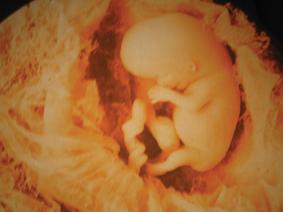

نقص حقنة «RH» يقضي علي حلم الامهات الحوامل للمرة الثانية في مولود جديد صحي، بعد أن اختفت هذه الحقنة من سوق الدواء واقتصر وجودها على كميات قليلة لا تتعدي الـ3 حقن بهيئة المصل واللقاح.

وحقنة RH 'عبارة عن تحليل دم تجريه الحامل قبل الولادة فإذا كانت مثلا فصيلة دمها B+ يدل على أنها فصيلة الدم B ويحتوى جسمها علىRH، أما إذا كانت فصيلة دمها B- فيدل ذلك على أنها فصيلة B أيضا ولكنها لا تحتوى على RH وهنا تكمن المشكلة، فالأب عادة يكون لديه RH والأم لا تملكه فيأخذ الجنين الصفة السائدة التى فيها الأب RH، فعند الولادة تكون كل الأوعية الدموية بمكان الولادة مفتوحة ويقوم الطبيب بقطع الحبل السرى بين الأم وطفلها، فتقع بعض من دماء الطفل على رحم وأوعية الأم ويتم الإختلاط بين دم الأم وطفلها وعندها تكتسب الأم RH من طفلها.

ويستجيب جهاز المناعة لدى الأم ويولد اجسام مضادة الموجود فى دم الطفل باعتباره جسما دخيلا وبالتالى ينتج اجساما مضادة للقضاء عليه وهو ليس مؤذيا خلال الحمل الأول وإنما تحدث المشكلة فى الحمل الثانى بطفل آخر ينتمى إلى فصيلة «الآر إتش» وذلك لوجود أجسام مضادة قد تكونت فى الحمل الأول حيث تعبر المشيمة وتهاجم خلايا دم الطفل وقد يؤدى ذلك إلى أصابة الطفل الثانى بفقر دم شديد وقصور فى القلب واحتباس السوائل ويمكن أن تصل للوفاة.

وأكدت استشارى النساء والتوليد على ضرورة إعطاء حقنة المضاد «الآر إتش» والتى تعمل على القضاء على جميع خلايا دم الطفل التى تتسرب فى مجرى دم الأم وذلك قبل أن يتمكن الجسم من إنتاج أية أجسام مضادة، وإشارة إلى ضرورة حقن الأم بالمضاد خلال 72 ساعة بعد الولادة وليس أكثر.